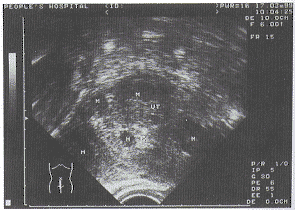

Ⅲ型为混合型27例,此型主要为多发性子宫肌瘤,粘膜下、肌壁间及浆膜下肌瘤同时存在。子宫增大,表面有突起,内部回声中低不均,过大肌瘤伴有超声衰减,子宫内膜弯曲,偏向一侧。此类较大粘膜下肌瘤易发现,较小的粘膜下肌瘤易漏诊(图3)。

E:内膜,其旁的M为粘膜下肌瘤,其余的M为肌瘤

图3 Ⅲ型 多发性子宫肌瘤